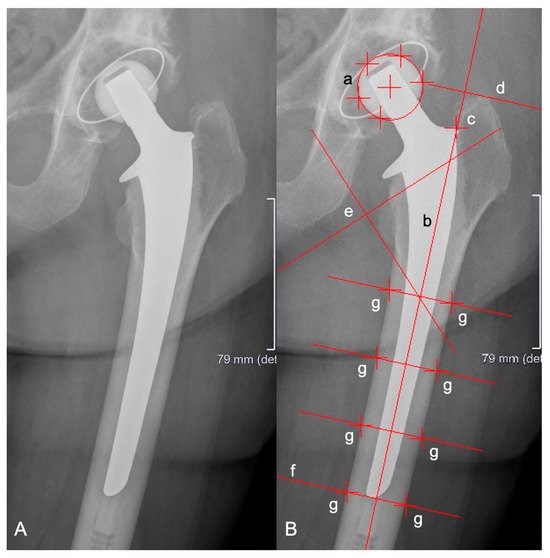

- Biedermann, R.; Krismer, M.; Stöckl, B.; Mayrhofer, P.; Ornstein, E.; Franzén, H. Accuracy of EBRA-FCA in the Measurement of Migration of Femoral Components of Total Hip Replacement. J. Bone Jt. Surg. Br. 1999, 81, 266–272. [Google Scholar] [CrossRef]

- Dammerer, D.; Blum, P.; Putzer, D.; Krappinger, D.; Liebensteiner, M.C.; Nogler, M.; Thaler, M. Subsidence of a Metaphyseal-Anchored Press-Fit Stem after 4-Year Follow-up: An EBRA-FCA Analysis. Arch. Orthop. Trauma. Surg. 2022, 142, 2075–2082. [Google Scholar] [CrossRef]